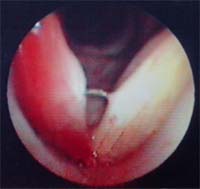

| 小学5年女児。バレーボール練習により、大声を出し続け出現。 矢印は結節、*は結節により圧迫され出来た、接触性潰瘍 母の愁訴:声にならない。発声持続時間:8秒間。 |

| 左図:硬そうなこぶが向かい合っている.. 右図:声を出す時、邪魔をする.隙間から気管が見える. 隙間から空気が漏れ、一呼吸で話せる時間は短くなる. |